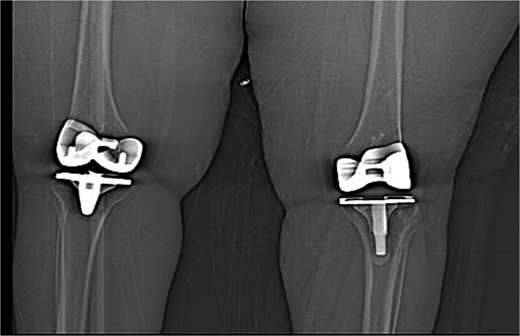

The case involves a 48-year-old obese woman with a body mass index (BMI) of 42, a known medical history of polio, and a baseline of bilateral knee hyperextension of 5º, who underwent bilateral staged TKA with posterior stabilized knee prosthesis in 2018 with a good functional level and outcome (Fig. 1).

Anteroposterior view of both knees post bilateral staged total knee arthroplasty.